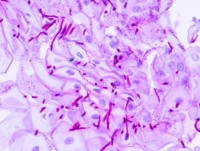

Az utóbbi időben több olyan tényezőt sikerült azonosítani, amelyek a candidiasis kórfolyamatában kiváltó (iniciátor) vagy a betegség kialakulását segítő (promoter) faktorként szerepel. A jelenlegi ismeretek szerint ezek a következők: Az antibiotikumok egy részének (penicillin, tetracyclin, erythromycin) huzamosabb időn át tartó szedése károkat okozhat a bélflóra érzékeny mikrobiális egyensúlyában. A hasznos és erjesztő munkát végző tejsavbaktériumok kiszorulásával az előnytelen, rothadási folyamatokat elindító mikrobák, valamint a sarjadzó gombafajok kerülnek túlsúlyba a béltraktusban.

Az antibakteriális szappan vagy tusfürdő hatóanyaga a kézmosás illetve tisztálkodás után is kifejti hatását az érintett területeken. Célzott, gombaellenes hatóanyagokat azonban csak ritkán tartalmaznak, így a bőrfelületen nagy lendülettel megindulhat a gombasejtek szaporodása. A lokális gombás betegségek (pl: körömágyban, fejbőrön, hajlatokban, nemi szervek tájékán) gyakorisága ugrásszerűen megnövekedett az antibakteriális szerek elterjedésével, és napjainkban e szerek már a szisztémás candidiasisért is felelőssé tehetők.